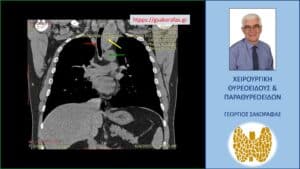

Αξονική τομογραφία – απεικόνιση σε κατά μέτωπο διατομή. Εμφανής η μεγάλου βαθμού διόγκωση και η κατάδυση σε βάθος του αριστερού λοβού (κίτρινο βέλος), που φθάνει στις παρυφές του αορτικού τόξου (πράσινο βέλος), με την τραχεία (κόκκινο βέλος) να απωθείται προς τα δεξιά από τον διογκωμένο αριστερό λοβό.